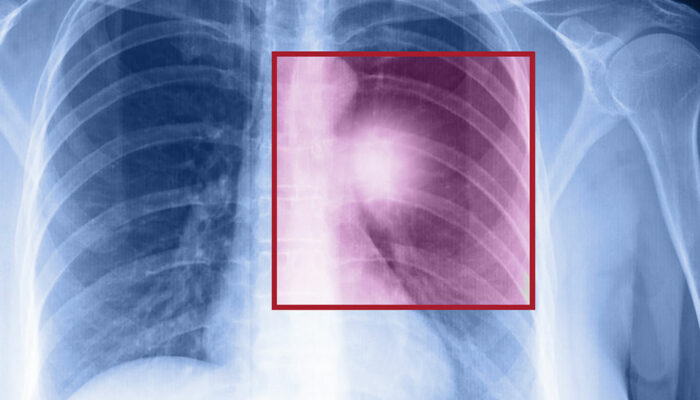

Lung cancer – Types, symptoms, and causes

When the cells in the lungs begin to abnormally multiply and grow, it results in cancer. Lung cancer is one of the leading causes of death in the world. And the risk of suffering from this life-threatening disease is even higher when one is a smoker. Herein, we discuss the various factors that come into play when it comes to lung cancer.

Types of lung cancer

There are two kinds of lung cancer:

- Non-small cell lung cancer

This is a catchall term that includes many varieties of this disease, like large cell carcinoma, squamous cell carcinoma, and adenocarcinoma. - Small cell lung cancer

This happens mainly to people who are heavy smokers, and it’s rarer than non-small cell lung cancer.